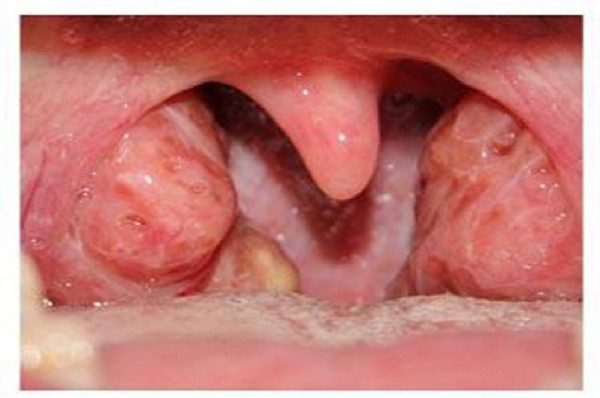

20af6f313e08a21ba66b8e784db8bb2aХоолой нь өвдөж үзээгүй хүн гэж байхгүй. Энэ өвчний албан ёсны нэр томъёо нь хоолойн бах буюу ангин юм. Хүмүүс энэ өвчний хор уршгийг сайн мэддэгүй болоод тэр үү, тэрбүр тууштай эмчилдэггүй. Тэгтэл энэ өвчин хүндэрхээрээ зүрх, бөөр, үе мөчиндөө орж хүндээр өвчлүүлдэг.

Хоолойн өвчнийг удаалгүй аль болох түргэн эмчлэх хэрэгтэй. Хоолой сэрвэгнэж, юм залгихад хөндүүрлэж бага зэрэг улайсан байх нь хоолой өвдөх анхны шинж тэмдэг юм. Эдгээр шинжүүд илрэх л юм бол тэр даруй арга хэмжээ авч эхлэх шаардлагатай. Хөөрүүлсэн халуун сүү хоолойг цочроодог учраас ийм үедээ ууж хэрэггүй. Хоолой хөндүүрлээд байвал өдрийн турш 2-3 ширхэг каланхоэны (тасалгааны ургамал) навч удаан зажилж ид. Энэ ургамал бараг айл бүрд бий.